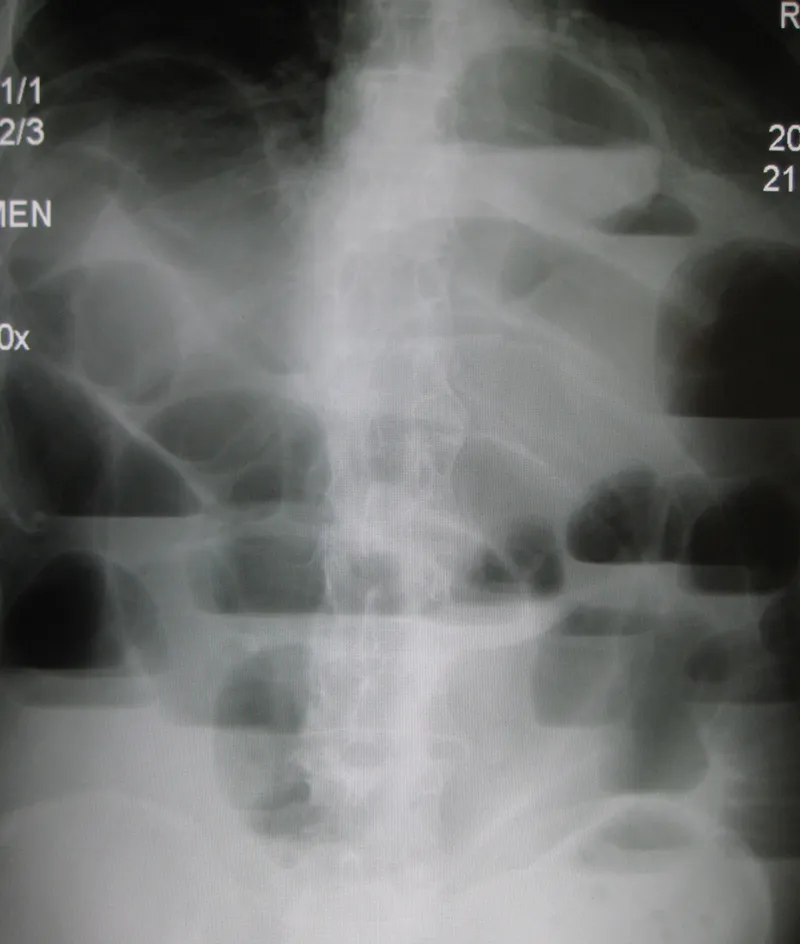

- Abdominal X-ray (AXR): First-line test. Shows generalized, uniform dilation of both small and large bowel; no transition point.

⭐ On imaging, paralytic ileus is distinguished from SBO by gas and dilation throughout both the small and large bowel, whereas SBO typically shows a clear transition point with distal bowel collapse.

- Differentiate from SBO via X-ray: ileus shows diffusely dilated bowel loops, while SBO has a clear transition point.